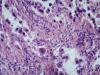

Опухоль легкого |

Карциноид...

Аденокарцинома со стелющимся типом роста (lepidic)

Тоже склоняюсь к бронхиолоальвеолярному раку.

Уважаемый Медик, добрый вечер! Поясните, пожалуйста, в чем существенная разница между БАР и предложенным мной вариантом? В своей работе я использую классификацию 2015 года, в которой БАР нет, это устаревший термин. Верно, с 2015г..БАР нет. В данном случае Аденкарцинома, lepidic тип👏 |